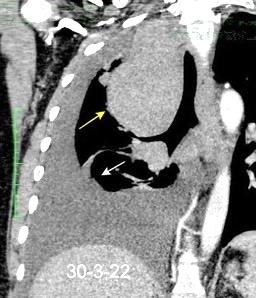

Síndrome de afectación postcardiaca (postcardiac injury)

Post infarto 1-7 % (Dressler)

Trauma cerrado Implantación marcapasos

Cirugía cardiaca. 17-31% (Post.pericardiotomía)

3707 pacientes 29 Derrames (0,78%) > de 25% del hemitórax

Todas menos 2 Izdos.

Angioplastia

By-pass coronario 21-10-03